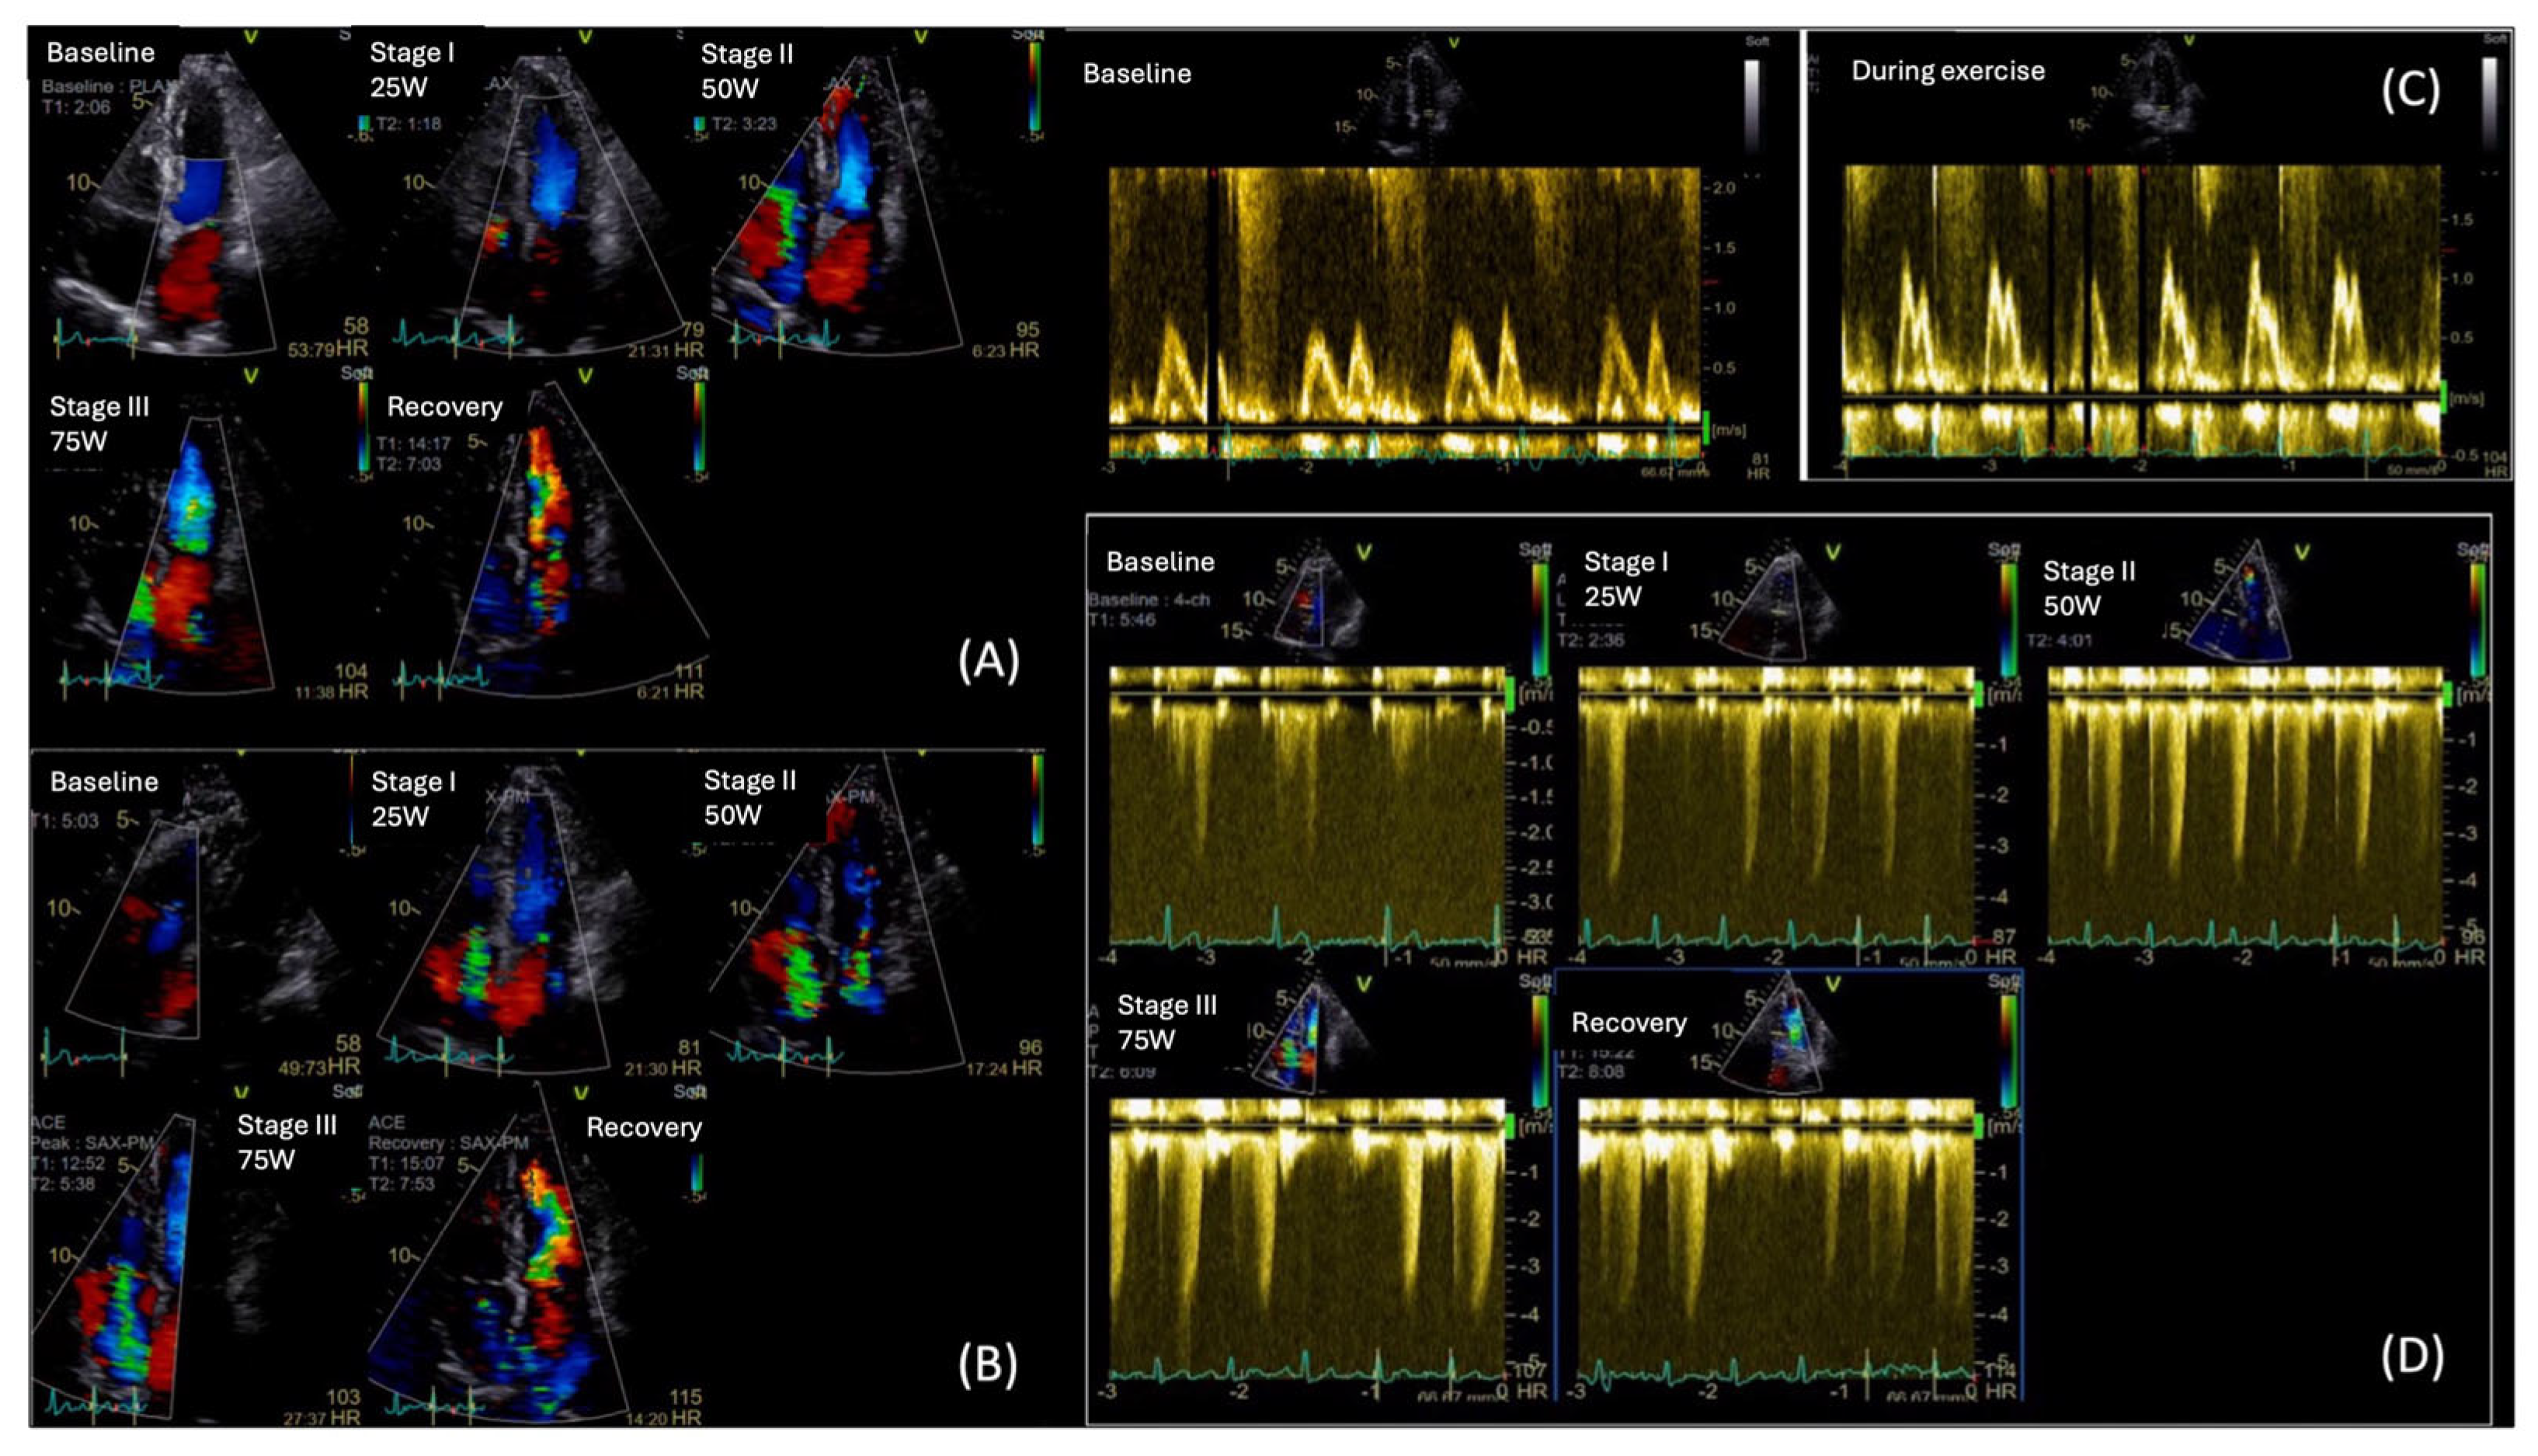

The key echocardiographic parameters of diastolic dysfunction include the transmitral E/A ratio, E/e’ ratio, early diastolic velocity (e’) using tissue Doppler imaging (TDI), left atrial (LA) volume index (LAVi), and the assessment of tricuspid regurgitation (TR) using Doppler ultrasound. The duration of uncontrolled DM correlates positively with the incidence and severity of diastolic dysfunction [40]. Jain et al. demonstrated a strong association between elevated hemoglobin A1C (HbA1c) levels and diastolic dysfunction. In their study, half of the participants with HbA1c >9.5% exhibited a restrictive filling pattern [43]. However, most studies report that DM patients with diastolic dysfunction present with impaired relaxation or pseudonormal filling patterns [38].

Initial studies showed decreased transmitral E/A ratio in patients with DM, even when LV mass remains normal [44]. The E/e’ ratio, which reflects LVFP, was found significantly elevated in patients with HbA1c levels ≥8.1% [40]. In agreement to previous studies, From et al. observed an independent association of DM duration of over four years with E/e’ > 15 [45]. Importantly, a septal E/e’ ratio >15 in diabetic patients is associated with the subsequent development of HF and increased mortality independent of CAD, HTN, or other echocardiographic parameters [46].

The use of LA volumes has proven more effective in detecting subclinical cardiac damage in DM patients. Over the past decade, previous studies in DM patients have confirmed common LA enlargement, as measured by LA volumes and indexes [46,50,51,52]. Recent evidence highlights a strong association between disease duration and both increased LA volume and impaired LA function [50]. These parameters constitute independent predictors of cardiovascular events in diabetic patients [46,49,51,53,54]. Notably, an increased LAVi ≥ 32 mL/m2 has been identified as an independent and incremental predictor of cardiovascular morbidity and mortality in diabetic patients without known cardiovascular disease [55].

Diastolic dysfunction in individuals with DM is associated with a worse prognosis, as these patients face a higher risk of developing HF, compared to their counterparts without diastolic dysfunction [45]. Optimizing DM treatment and reducing HbA1c levels may lead to improvements in diastolic dysfunction, potentially delaying the progression to HF [56] (Figure 1).